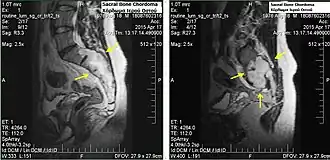

Chordomas can arise from bone in the skull base and anywhere along the spine. The two most common locations are cranially at the clivus and in the sacrum at the bottom of the spine.[2] Very rarely, chordomas present outside of the skull base or spine; these are called extra axial chordomas.[3]

In most cases, complete surgical resection followed by radiation therapy offers the best chance of long-term control.[17] Incomplete resection of the primary tumor makes controlling the disease more difficult and increases the odds of recurrence. The decision whether complete or incomplete surgery should be performed primarily depends on the anatomical location of the tumor and its proximity to vital parts of the central nervous system.[18]

Chordomas are relatively radioresistant, requiring high doses of radiation to be controlled. The proximity of chordomas to vital neurological structures such as the brain stem and nerves limits the dose of radiation that can safely be delivered. Therefore, highly focused radiation such as proton therapy and carbon ion therapy are more effective than conventional x-ray radiation.[19]

In one study, the 10-year tumor free survival rate for sacral chordoma was 46%.[25] Prognosis depends on many different factors. With appropriate treatment, many chordoma patients will live for a decade or more, and some can be cured.[26]

Sacral chordomas make up 2 to 4% of all primary bone tumours and 44% of all primary sacral tumours, thus making it the most common malignant sacral tumor. About 50 to 60% of chordomas are located in the sacrococcygeal region. Males aged between 40 and 50 years are twice as likely as women to get sacral chordoma.[28]